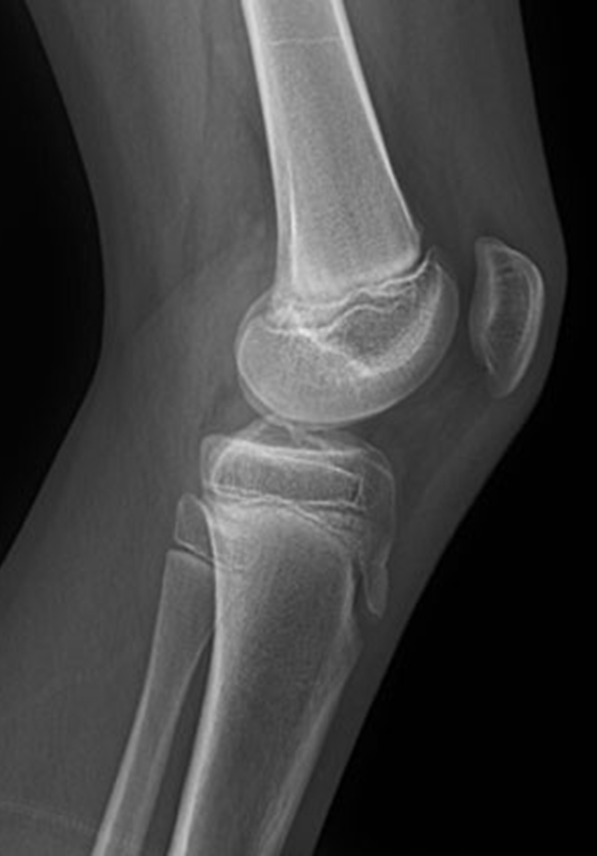

Trauma and Non Trauma AP Knee

•Evidence of proper collimation and the presence of a side marker placed clear of the anatomy of interest

•Knee fully extended if patient’s condition permits

•Entire knee without rotation

•Femoral condyles symmetric and tibia intercondylar eminence centered

•Slight superimposition of the fibular head if the tibia is normal

•Patella completely superimposed on the femur

•Open femorotibial joint space, with interspaces of equal width on both sides if the knee is normal

•Bony trabecular detail and surrounding soft tissues

Anatomy of the knee

Lateral Rotation, the fibular head is under the tibia, if patella is towards lateral side usually means it is laterally rotated.

Joint space is not open enough

The width of the joint space is not equal

REPEAT FOR LATERAL ROTATION

Not enough superimposition of the fibular head

Patella is in the center! good! equal distance of joint space/platoes which is good

ACCEPTABLE BECAUSE EVERYTHING ELSE IS GOOD! PATIENT COULD HAVE A MORE SEPARATED FIBULAR HEAD! THEIR ANATOMY IS DIFFERENT. CENTERING IS GOOD